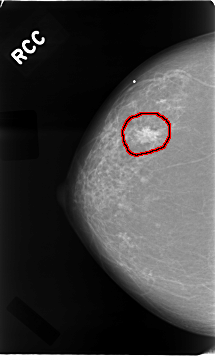

C_0016_1.RIGHT_MLO

C_0016_1.RIGHT_CC

RIGHT_CC LINES 4680 PIXELS_PER_LINE 2792 BITS_PER_PIXEL 12 RESOLUTION 50 OVERLAY

FILE: C_0016_1.RIGHT_CC.OVERLAY

TOTAL_ABNORMALITIES 1

ABNORMALITY 1

LESION_TYPE MASS SHAPE IRREGULAR MARGINS SPICULATED

ASSESSMENT 5

SUBTLETY 5

PATHOLOGY MALIGNANT

TOTAL_OUTLINES 1

BOUNDARY